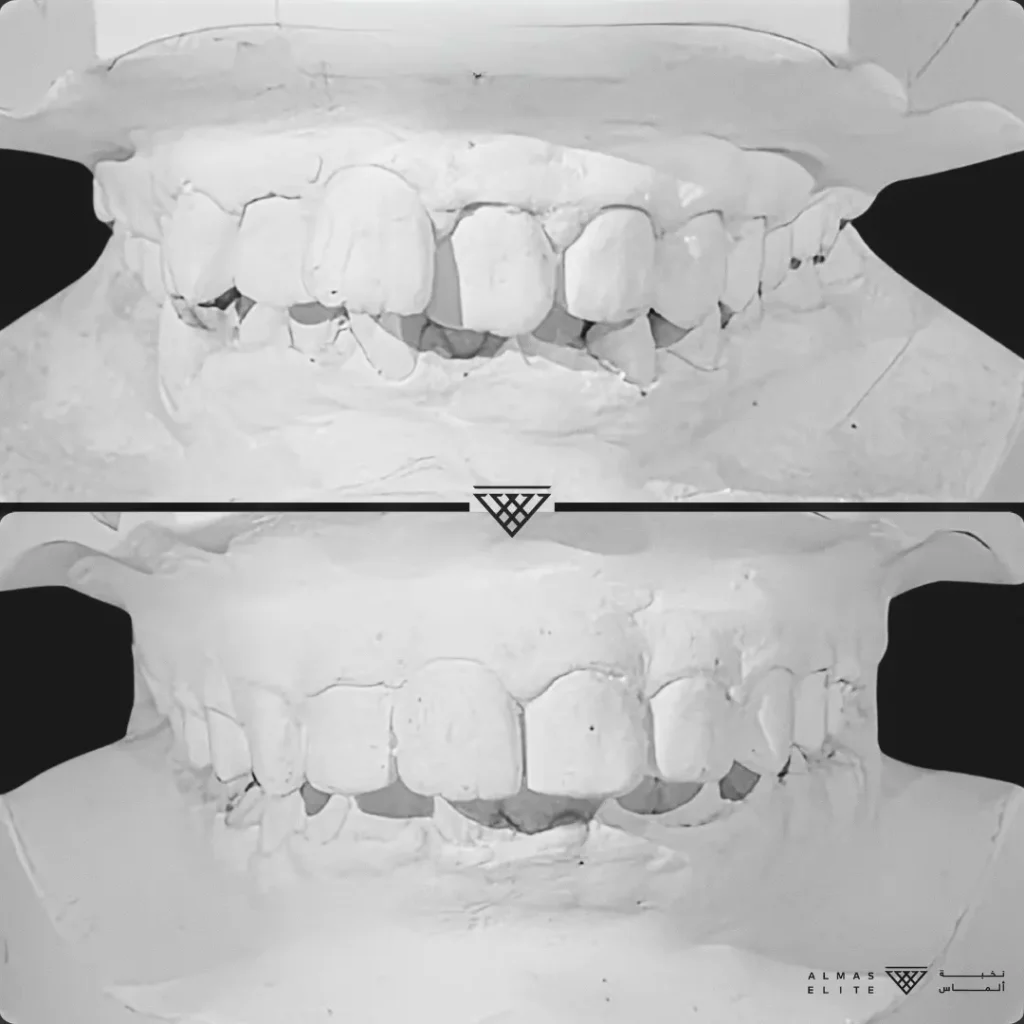

- تشخيص دقيق يشمل الأشعة والتحليل الرقمي للأسنان والفكين.

٢) التقييم والتشخيص الشامل

يشمل صور الأشعة والتحليل الرقمي للأسنان والفكين للوصول إلى تشخيص دقيق.

٣) وضع خطة علاجية مخصصة

تتضمن نوع الجهاز الأنسب، المدة المتوقعة، وتكلفة العلاج، مع شرح واضح لما يمكن توقعه أثناء رحلة التقويم.